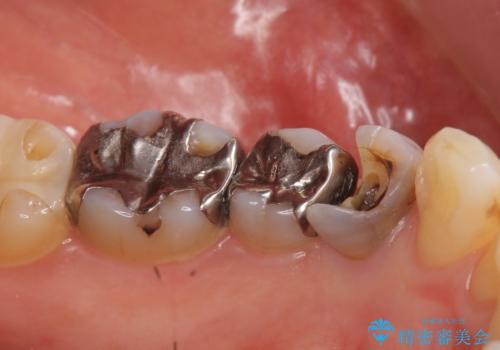

- 左下の詰め物が取れてしまったので治療したい、ついでに銀歯も白くしたいといらっしゃった方の症例です。

銀歯及び虫歯を除去後、オールセラミッククラウンによる補綴を行いました。